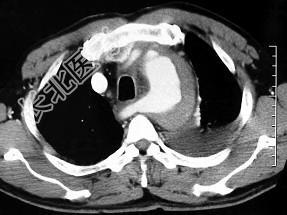

- 单项选择题男,58岁, 有高血压病史,突发胸背剧痛, CT扫描如图,其最可能的诊断为 ( )

E、主动脉夹层动脉瘤